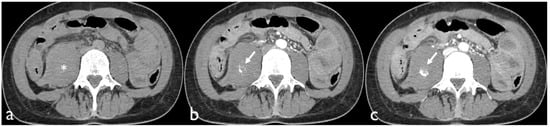

Active bleeding on CTA can be recognized as a focal area of higher density (with similar HU values to the abdominal aorta or major adjacent arteries) within the hematoma in arterial phase images, which is enlarged in venous phase images and not present in baseline unenhanced images (Figure 1) [18].

Figure 1. Non-contrast CT image (a) of a patient presenting with a hematoma of the right iliopsoas muscle extending into the retroperitoneal space (*). Contrast-enhanced axial CT images show active bleeding in the arterial (b) and portal phase (c).